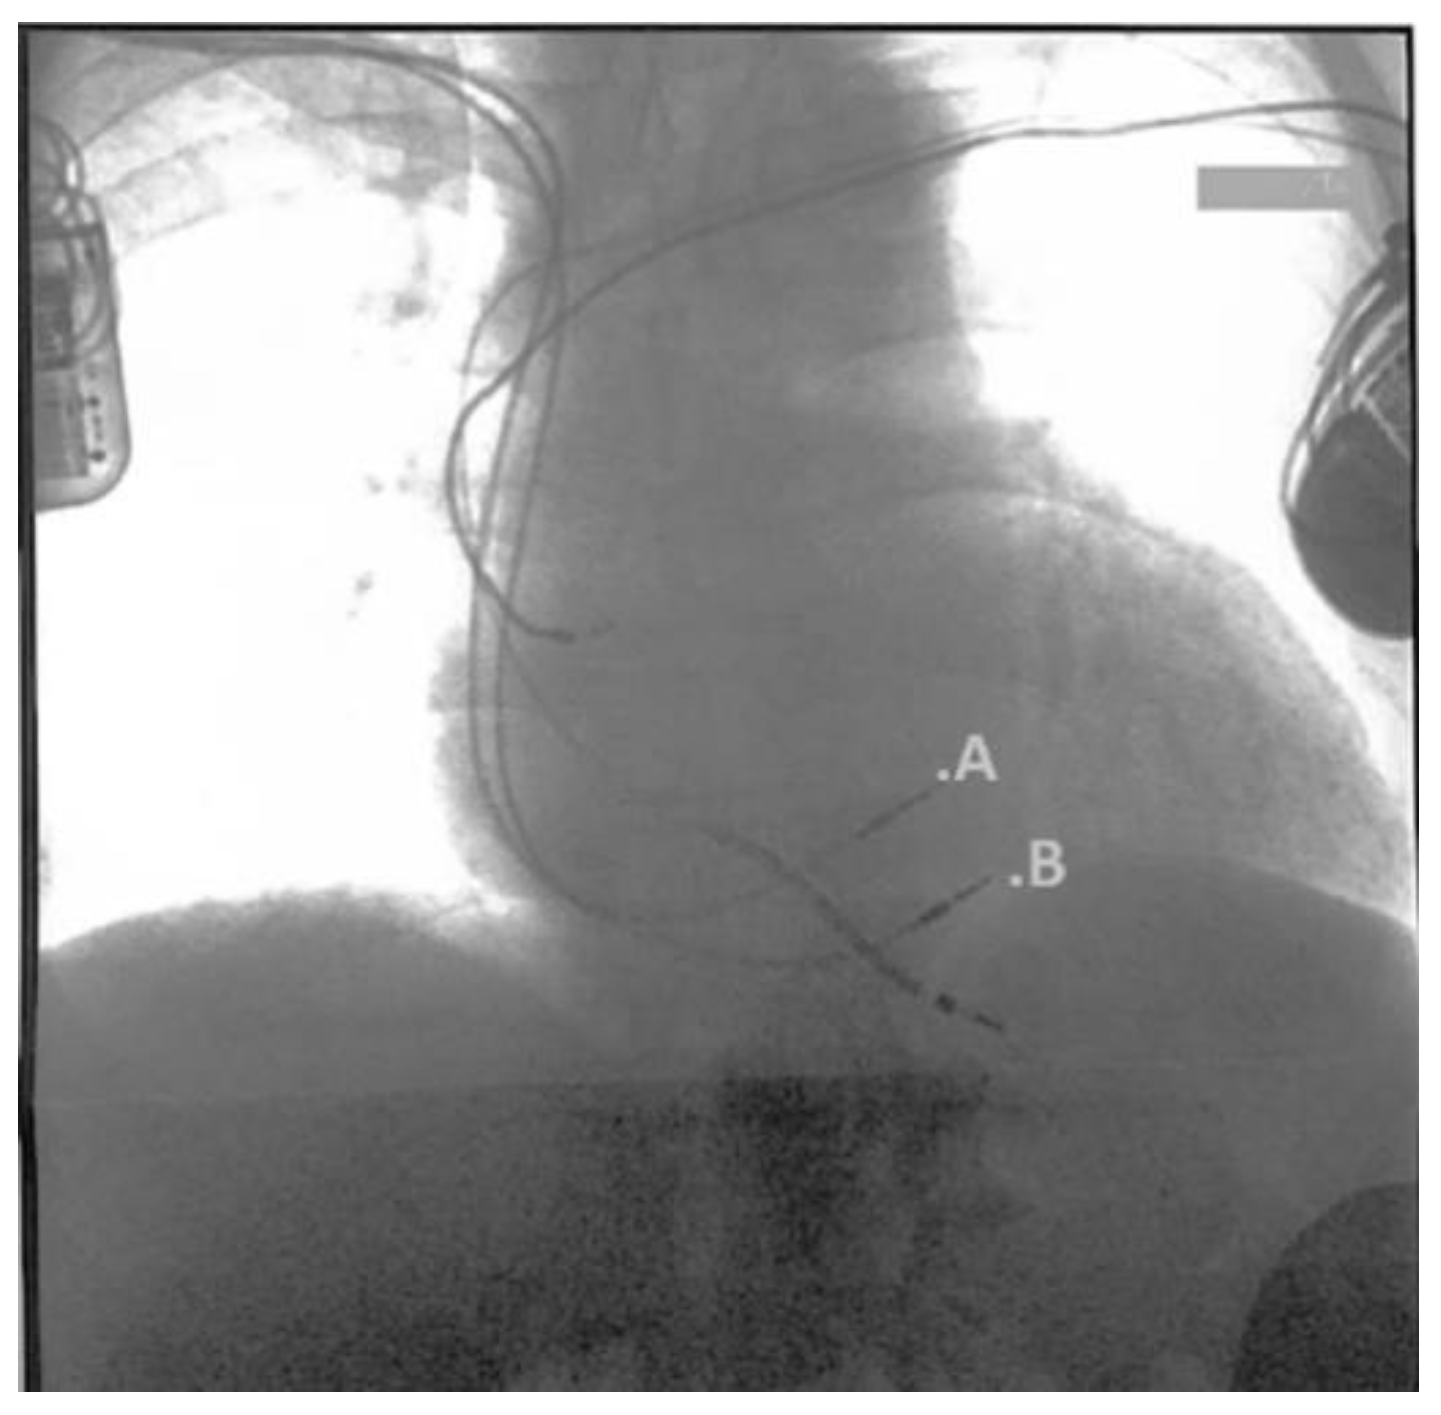

Waiting for the Transplant Center’s response, we showed the patient two different solutions for the HF treatment: the LVAD or the less invasive Cardiac Contractility Modulation (CCM) device, to treat the symptoms and improve his quality of life. The patient refused the LVAD as it was too invasive and accepted a CCM implant (Figure 3).

Figure 3. This RX picture shows the two active fixation leads placed on the RV septum approximately 2cm between. In this case, A. is the Right Ventricular (RV) lead marker, and B. is the Local Sense (LS) lead marker.